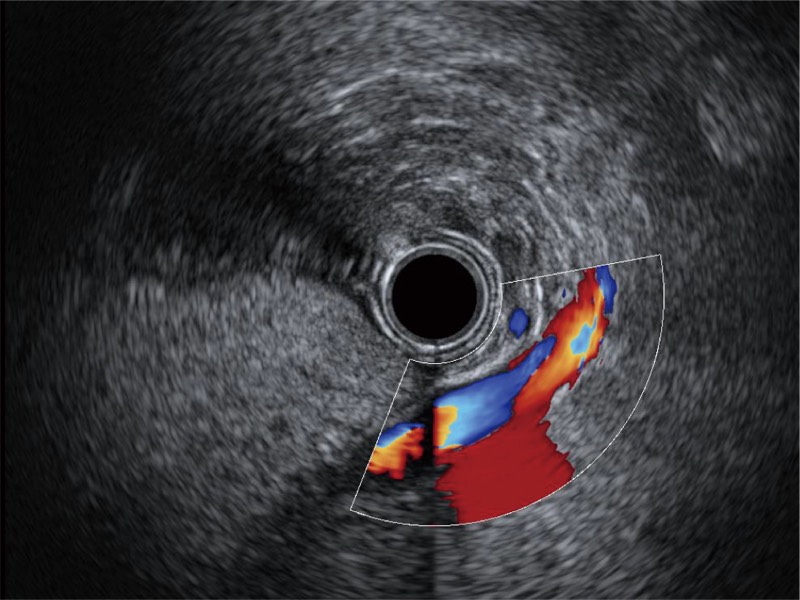

食管内间质瘤清晰显像